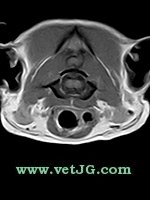

RESONANCIA MAGNÉTICA

AXIAL